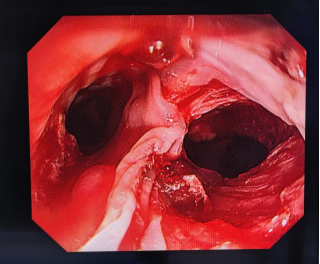

经过全面评估与反复研讨,专家团队决定采用Tubeless(无管)新技术,为患者实施“胃镜下食管异物取出+外科手术食管穿孔修补术”。手术中,消化内科蒋欢副主任医师凭借娴熟的内镜操作技术,顺利将尖锐枣核取出。随后,针对枣核造成的巨大食管破口,心胸外科陈均副主任、郑实谊副主任医师沉着应对、精准操作,采用Tubeless技术,为其成功实施食管穿孔修补术。术后,患者平安返回病房,接受精细化监护与管理。